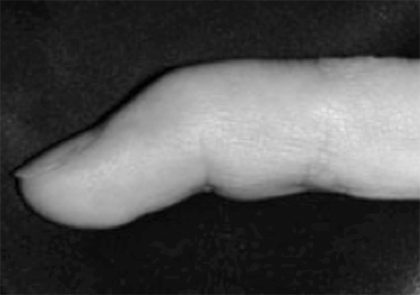

L’engruiximent i la constricció de la beina sinovial impedeix el lliscament fàcil dels tendons que flexionen els dits.